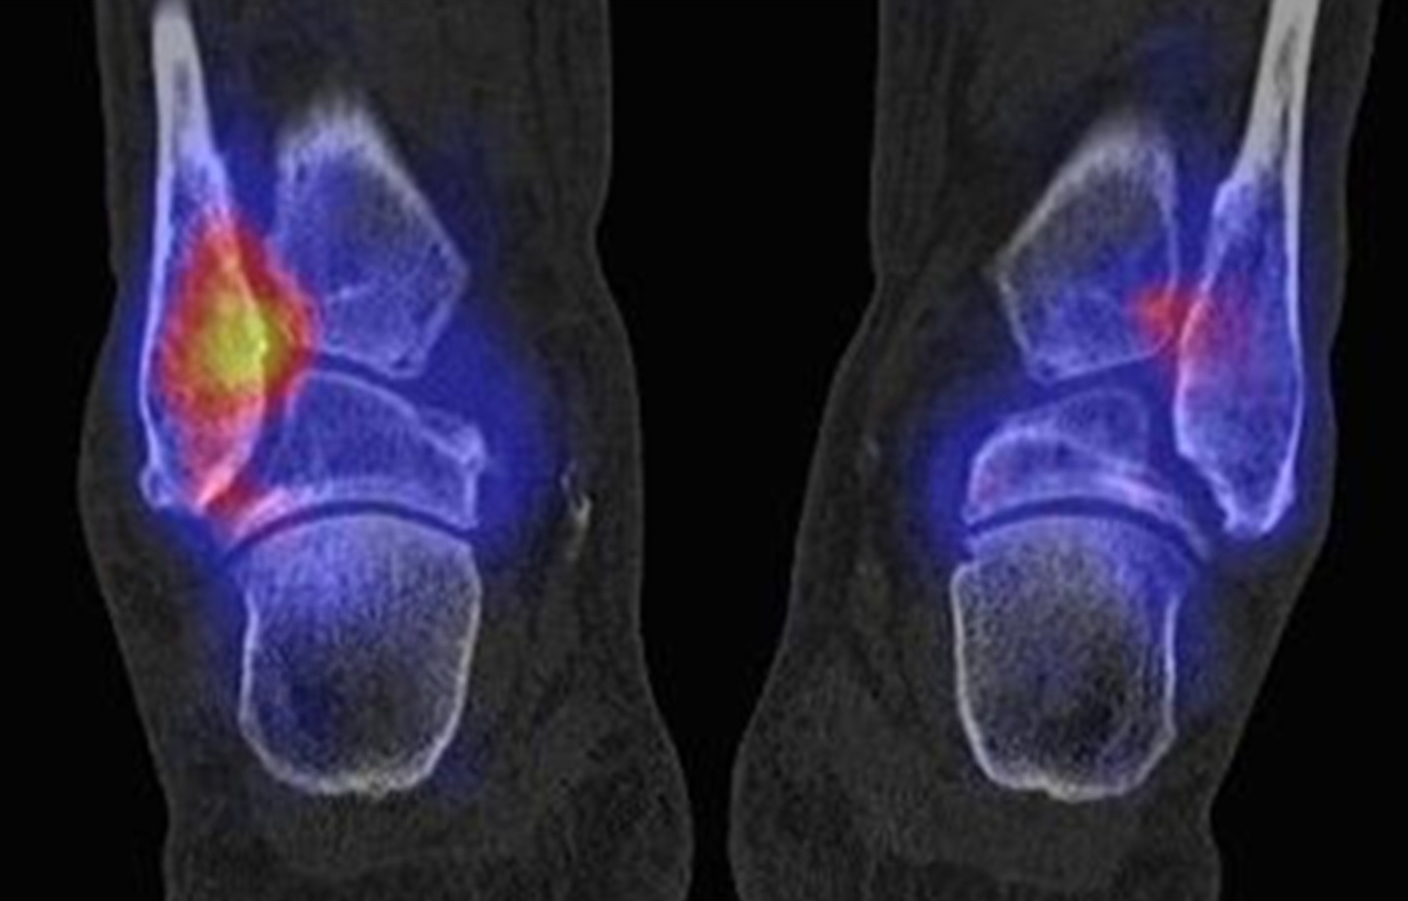

Abbildung 1.8.

Abbildung 1.8.a und b: Akute Arthritis bei bekannter Gicht in beiden OSG: links die Früh-/Weichteilphase; rechts die Mineralisations­phase. Deutliche, entzündlich bedingte Mehranreicherungen in der Früh-/Weichteilphase. In der Mineralisation­sphase erkennt man die entzündliche Mitreaktion der subchondralen Gelenkabschnitte.

Zum Lesen der Bildbeschreibung und zur Vollansicht bitte das Bild anklicken. Bild: H. C. Rischke

Abbildung 1.8.c - e: Akute Arthritis in beiden OSG, rechts > links. Im SPECT/CT erkennt man die Mitreaktion der subchondralen Gelenkabschnitte. Die Arthritis ist so akut, dass (noch) keine ossären morphologischen Veränderungen im CT abgrenzbar sind.

Zum Lesen der Bildbeschreibung und zur Vollansicht bitte die Bilder anklicken. Bilder: H. C. Rischke